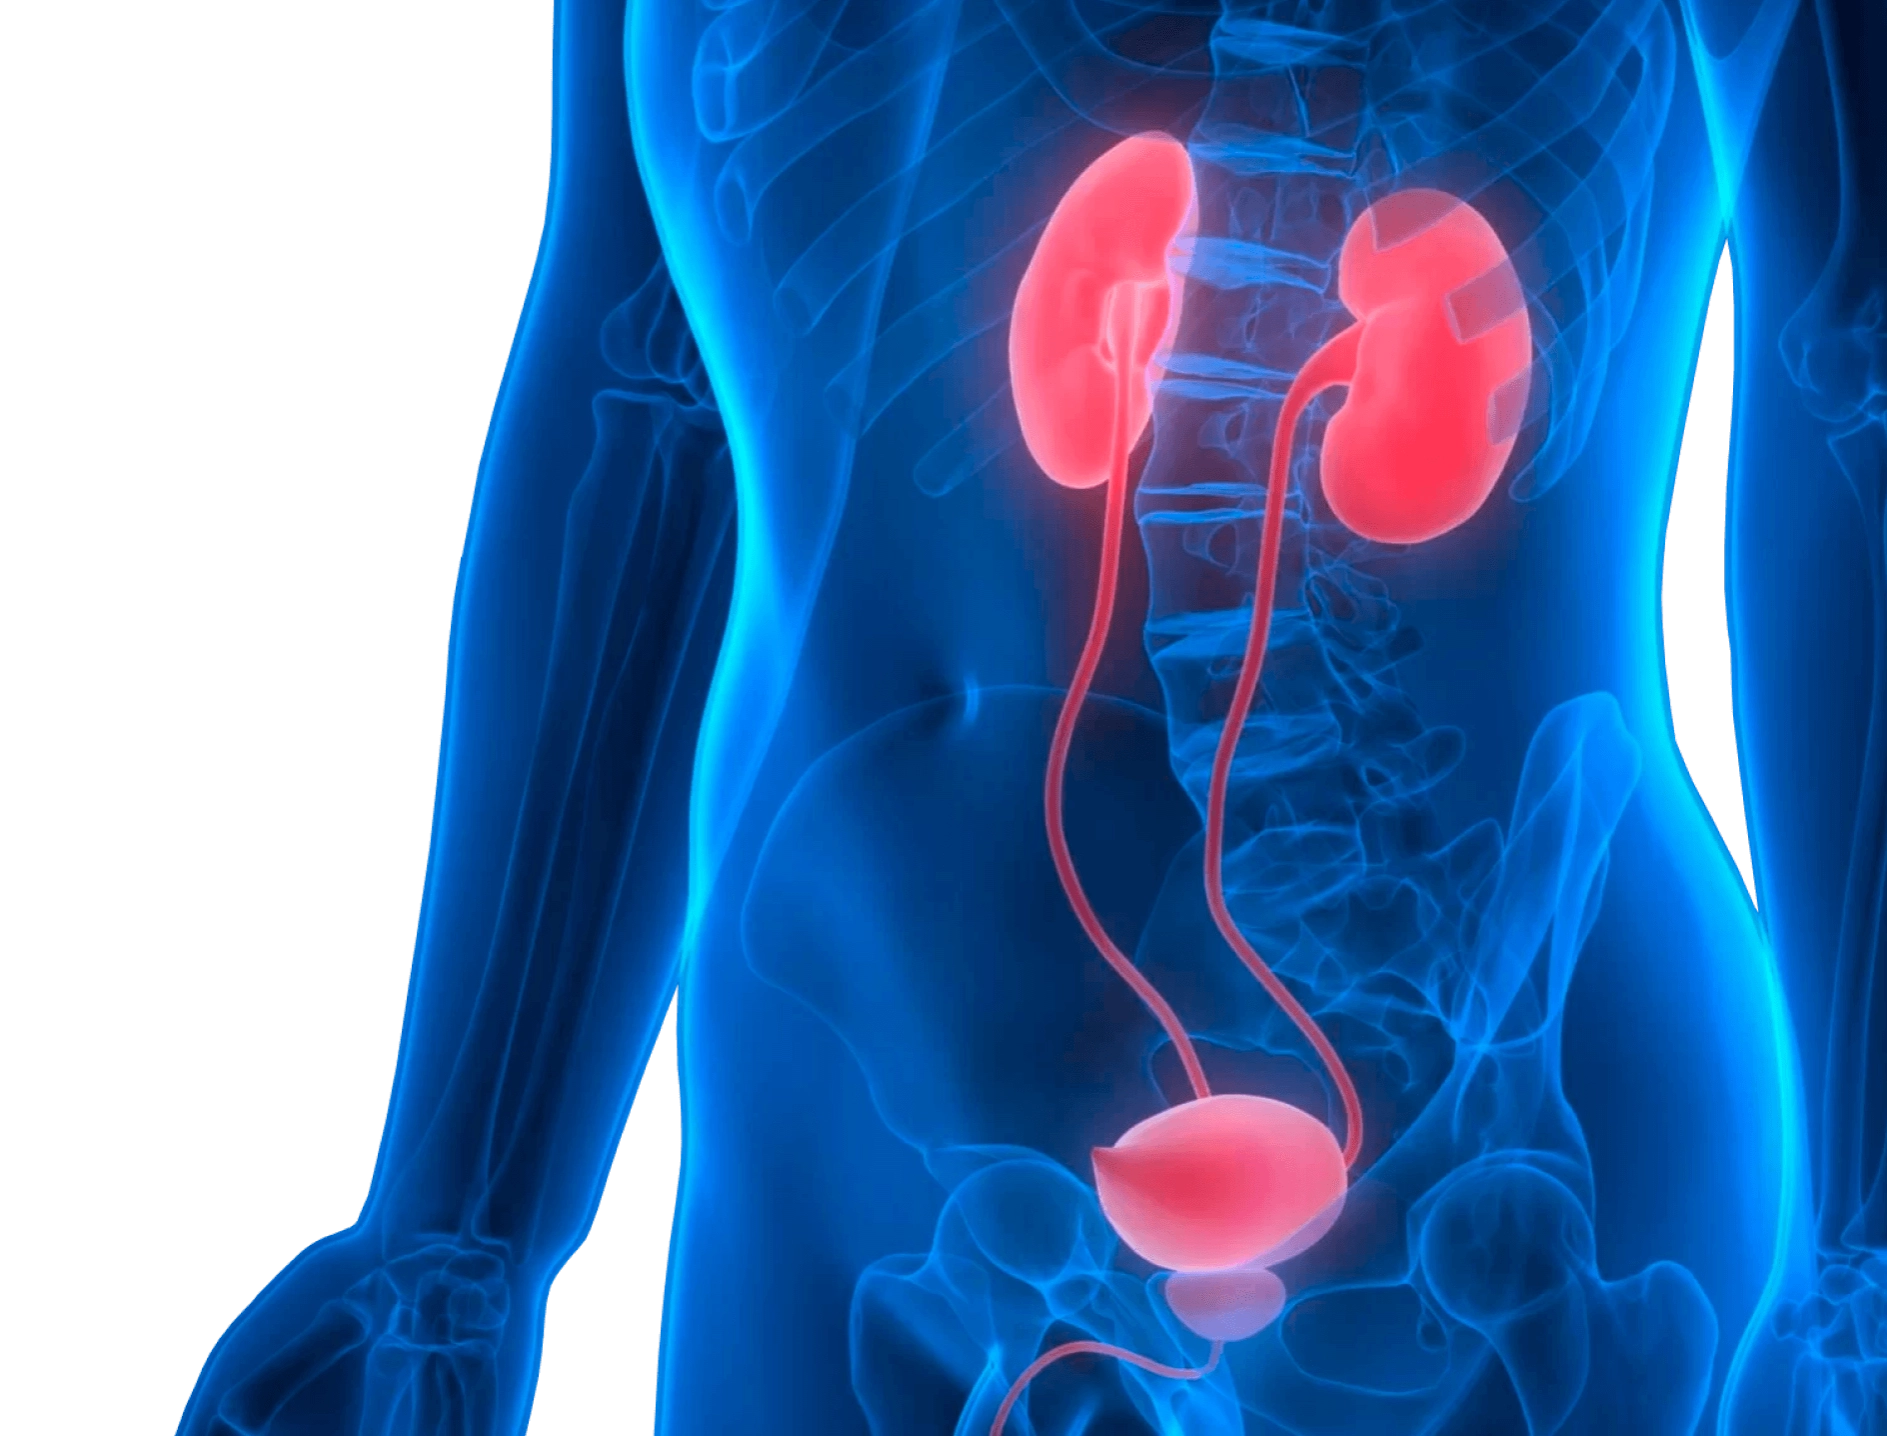

Специалист помогает избавиться от эректильной дисфункции, нарушений эякуляции (преждевременное семяизвержение, задержка, отсутствие). Врачи этой специальности занимаются проблемами мужского бесплодия. Андролог-хирург помогает устранить врожденные аномалии мужской мочеполовой сферы (гипоспадия, эписпадия – пороки развития уретры, мочеиспускательного канала).

- пальпация пениса, мошонки, области паха, почек;

- мануальное ректальное обследование простаты.

При необходимости врач на дому может провести исследование с помощью портативного аппарата УЗИ, взять биоматериал для лабораторных анализов. После осмотра, постановки диагноза, специалист делает назначения.